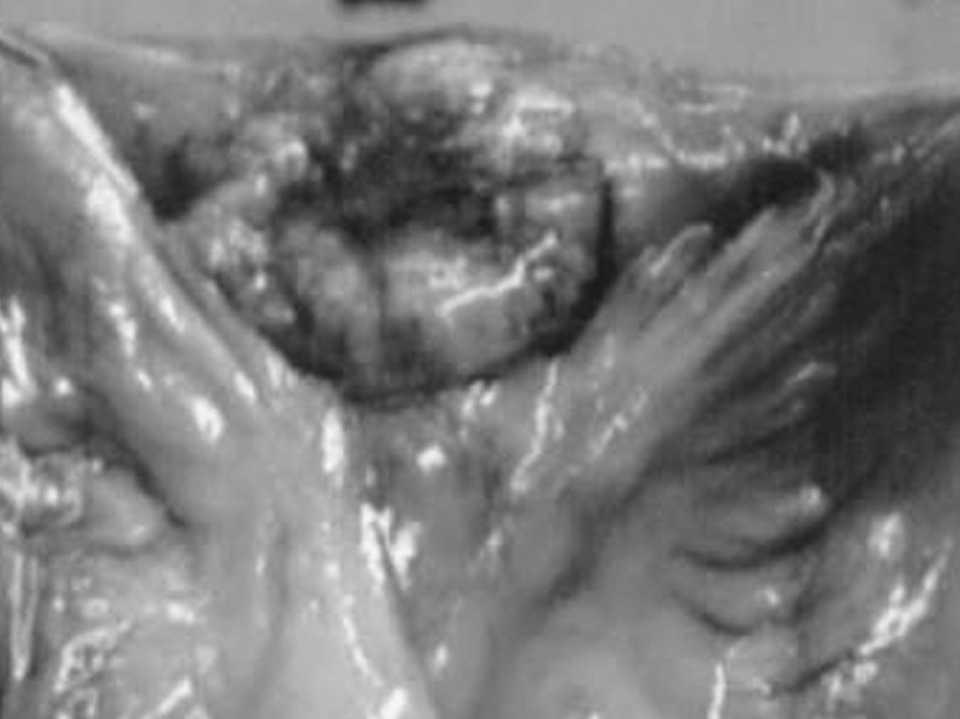

Durante el ingreso presenta, de forma súbita, dolor en el miembro inferior izquierdo, frialdad sin compromiso vascular, junto con equimosis cutánea, vesículas con exudación de líquido serohemorrágico no maloliente y crepitación a la palpación. Se confirma una infección necrosante de partes blandas, con presencia de bacterias de origen intestinal en los tejidos afectos. En la tomografía computarizada se observa la disección que genera el gas producido en la extremidad inferior izquierda (fig. 1).

Fig. 1.